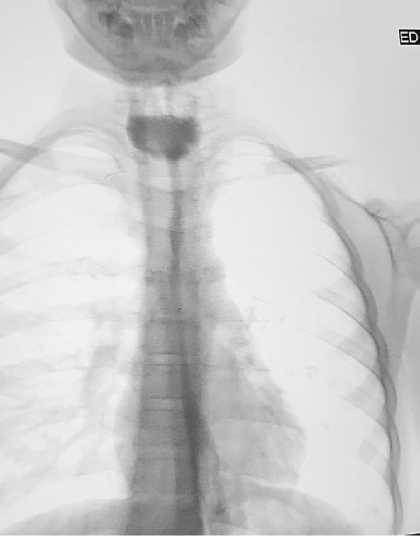

Эндоскопические методы лечения (бужирование и баллонная дилатация), применялись у всех пациентов как первый этап терапии. У большинства больных достигалось временное улучшение проходимости пищевода, однако при протяжённости рубцовой стриктуры более 3 см (Рисунок 1.) отмечалась высокая частота рецидива дисфагии.

Рисунок 1. Рентген снимок стриктуры пищевода с контрастным веществом